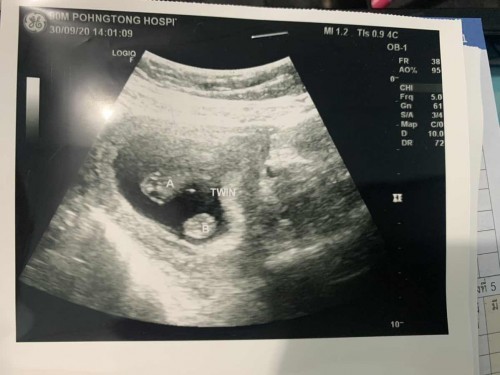

บ้านนี้ก็แฝดจ้าใบนี้ซาวตอน8wคะแต่ตอนนี้17wแล้วจ้า

แฝดหญิงจ้า 20 วีคแล้ว

แฝดญญ ค่ะ 32วีร